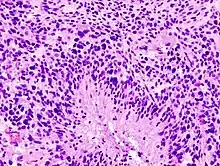

Glioblastoma (histology slide)

Glioblastomas are characterized by the presence of small areas of necrotizing tissue that are surrounded by anaplastic cells. This characteristic, as well as the presence of hyperplastic blood vessels, differentiates the tumor from grade 3 astrocytomas, which do not have these features.